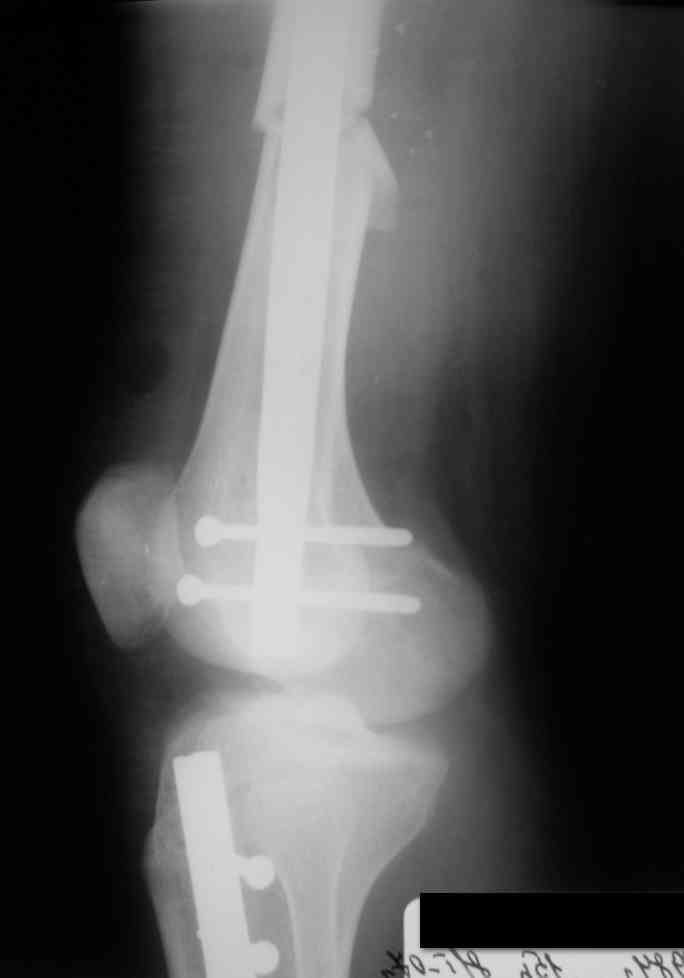

Дорогой Александр. Имею скромный опыт использования системы Fixion при переломах плеча, бедра и тибии. Всего 18 наблюдений с сентября 2006 г. Результаты отличные. Гвоздь индивидуален для каждого медуллярного канала. Легко имплантируется как в узкий, так и в деформированный канал. Это позволяет применять метод интрамедулярного остеосинтеза без ненужных потерь времени операции, флюороскопии и реально снижает крвопотерю и операционный риск. Удаление происходит без проблем. Особенно интересны больные с ипсилатеральными переломами бедра и голени.

В отношении ранней нагрузки при спиральных переломах лучше не торопиться. По данному случаю необходимо достигнуть исчезновения щели между штифтом и внутреним кортексом по Rg. А так картинка прекрасная - и длина сегмента и репозиция. Можно поздравить, коллега!